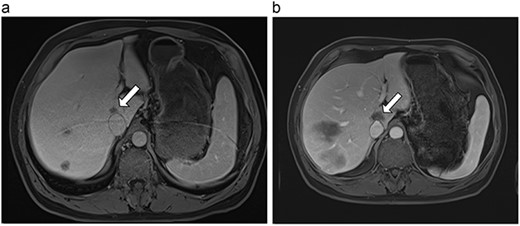

(a) Pre-ablation MRI demonstrating 15 mm lesion in caudate lobe of liver (image degraded by motion artifact). (b) Post-ablation MRI (20 days postoperatively) demonstrating 35 mm complete ablation of caudate lesion (image degraded by motion artifact).

| 2 (4a,b) | 67, M | Colon adenocarcinoma | 8 cycles capecitabine and oxaliplatin | 6 | Laparoscopic microwave ablation | 15 | 35 | 20 | 6 | No |